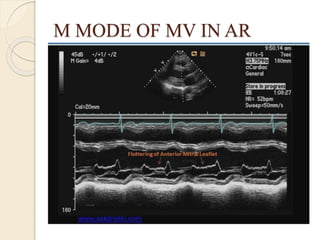

M MODE OF MV IN AR

INDIRECT SIGNS  IncreasedEPSS : maximal anterior motion of MV in early diastole and the posterior motion of IVS is >7mm or >1cm  High frequency fluterring of AML  Reversed diastolic curvature of the AML  Jet lesion on septum or mitral valve

M MODE OFMV IN AR